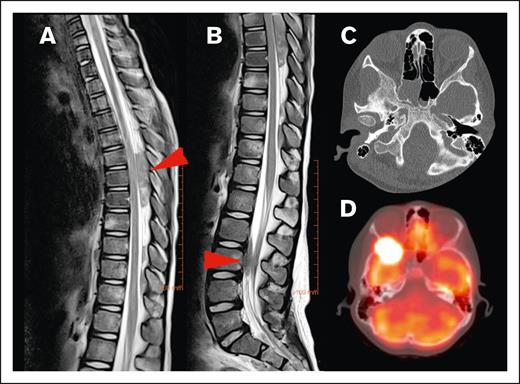

Different origins of CNS HL lesions. (A) Tumor originating from bone (vertebral body of T12, L1, and L2). (B) Unclear tumor origin but very likely bone, with circumferential involvement and an associated soft tissue component. (C) Paravertebral tumor mass of the upper thoracic spine infiltrating through the right neuroforamen, demonstrated by the red arrow, likely originating from soft tissue.

Most lesions (92.7%) extended through the neural foramina of either the vertebrae or sacral bone; 2 lesions did not extend through the neural foramina, and 2 lesions could not be evaluated (Figure 4). Thirty-one lesions entered the spinal canal. Of these, 54.8% caused displacement of the spinal cord, 25.8% were adjacent to the spinal cord but did not cause displacement, and 19.4% did not contact the spinal cord (Figure 5). None of the lesions infiltrated into the spinal cord itself. Spinal cord edema was evaluated for patients who had MRI available (17 of 31 lesions). Among these evaluable lesions, only 12.9% had evidence of spinal cord edema.